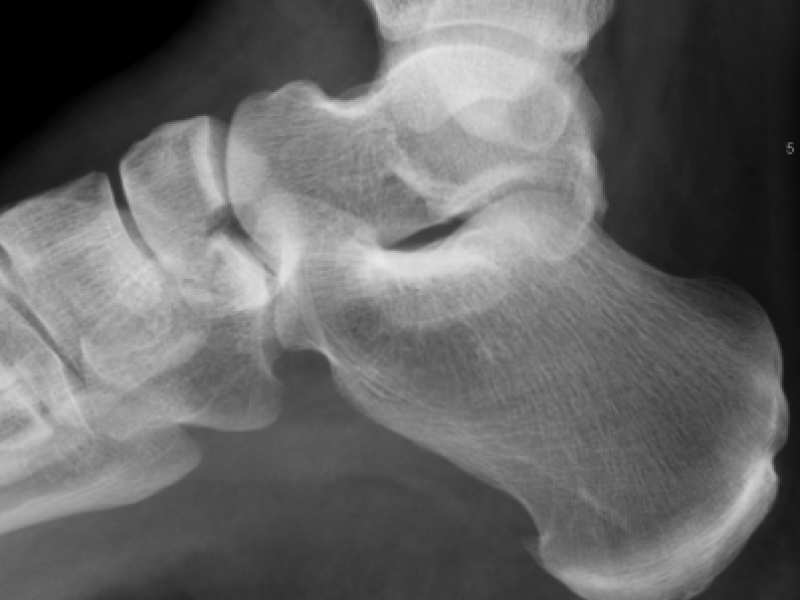

A 60 year old female presents with right foot pain following